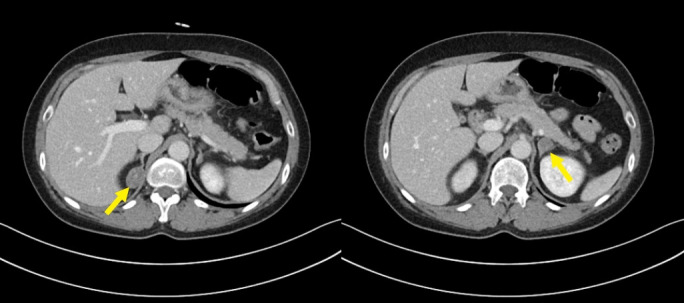

Primary aldosteronism (PA) is the most common cause of secondary hypertension and increases the morbidity and mortality associated with cardiovascular diseases. When PA coexists with autonomous cortisol secretion (ACS), the cardiovascular risk increases significantly, especially in cases of bilateral adrenal adenomas with asymmetric hormone secretion, which poses diagnostic and therapeutic challenges. A 50-year-old female presented with hypertension and hypokalemia. PA was diagnosed based on elevated aldosterone levels, suppressed plasma renin activity, and the results of various dynamic endocrine tests. Imaging revealed bilateral adrenal adenomas, and adrenal venous sampling (AVS) confirmed aldosterone hypersecretion from the left adrenal gland and cortisol hypersecretion from both adrenal glands. The patient subsequently underwent left adrenalectomy, which resolved the aldosterone hypersecretion and normalized blood pressure and potassium levels. However, the cortisol hypersecretion persisted. This case highlights the importance of AVS in identifying the sources of hormone secretion and enabling targeted surgical treatment while avoiding bilateral adrenalectomy, which can lead to lifelong adrenal insufficiency. Comprehensive endocrine evaluation, including ACS assessment, in patients with PA is essential to help reduce the cardiovascular risks associated with PA and ACS and thus improve treatment outcomes.